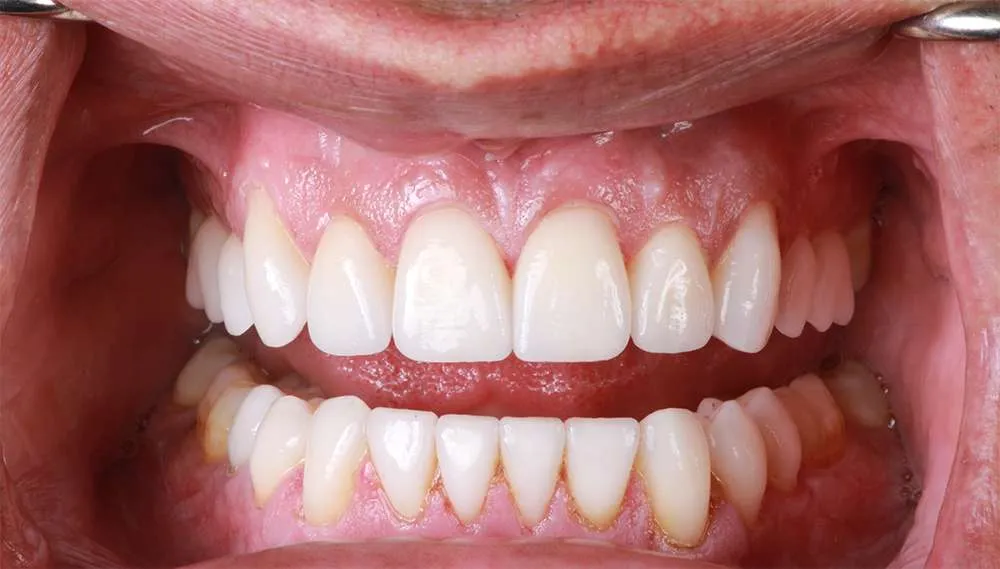

Real Stories, Real Results: Case Studies Showcasing How Our Personalized Approach Transforms Smiles and Lives

Complex Cases

Witness the Remarkable Changes We Can Achieve